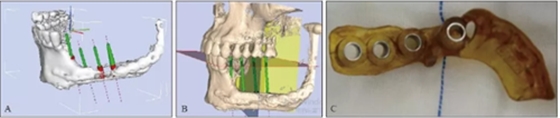

2016年4月27日根據(jù)患者條件設(shè)計(jì)并3D打印數(shù)字化種植導(dǎo)板(圖4)

并于左側(cè)腓骨移植區(qū)植入4顆Nobel Active 4.3 mm×11.5 mm種植體+RP 4.5 mm復(fù)合基臺(tái)(型號(hào)36626)(圖5)。